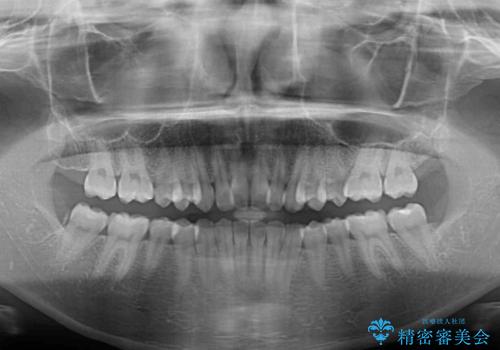

- 上の前歯が前方に飛び出していることを気にして来院された患者様です。

奥歯の咬み合わせをチェックすると、上顎歯列が相対的に前方に位置しているため、補助装置を用いて上顎歯列を確実に後方に移動させ、インビザラインで歯列を整えて行くこととしました。